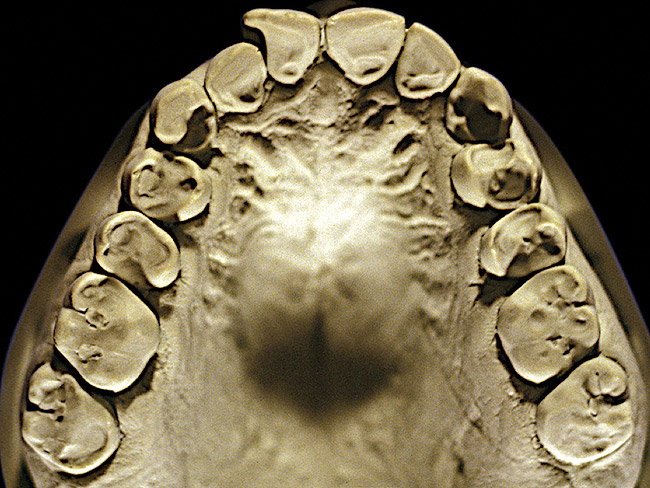

Figure 5  Moderate NCLTS from bruxism, maxillary arch.

The patient shown in Figure 3 and Figure 4 exhibited severe NCLTS from bruxism. Examination of the casts indicated that the NCLTS was progressively greater toward the anterior teeth. Cupping and cratering was not present because there was no secondary cause. Figure 5 and Figure 6 detail another bruxism patient, but to a lesser degree and one with cupping/cratering caused by toothpaste. The cups or craters were not caused from bruxism because the teeth could not touch the bottom of the invaginations. In both featured patients, upon hand-articulating the casts, the NCLTS facets matched up and the diagnosis of bruxism was confirmed.